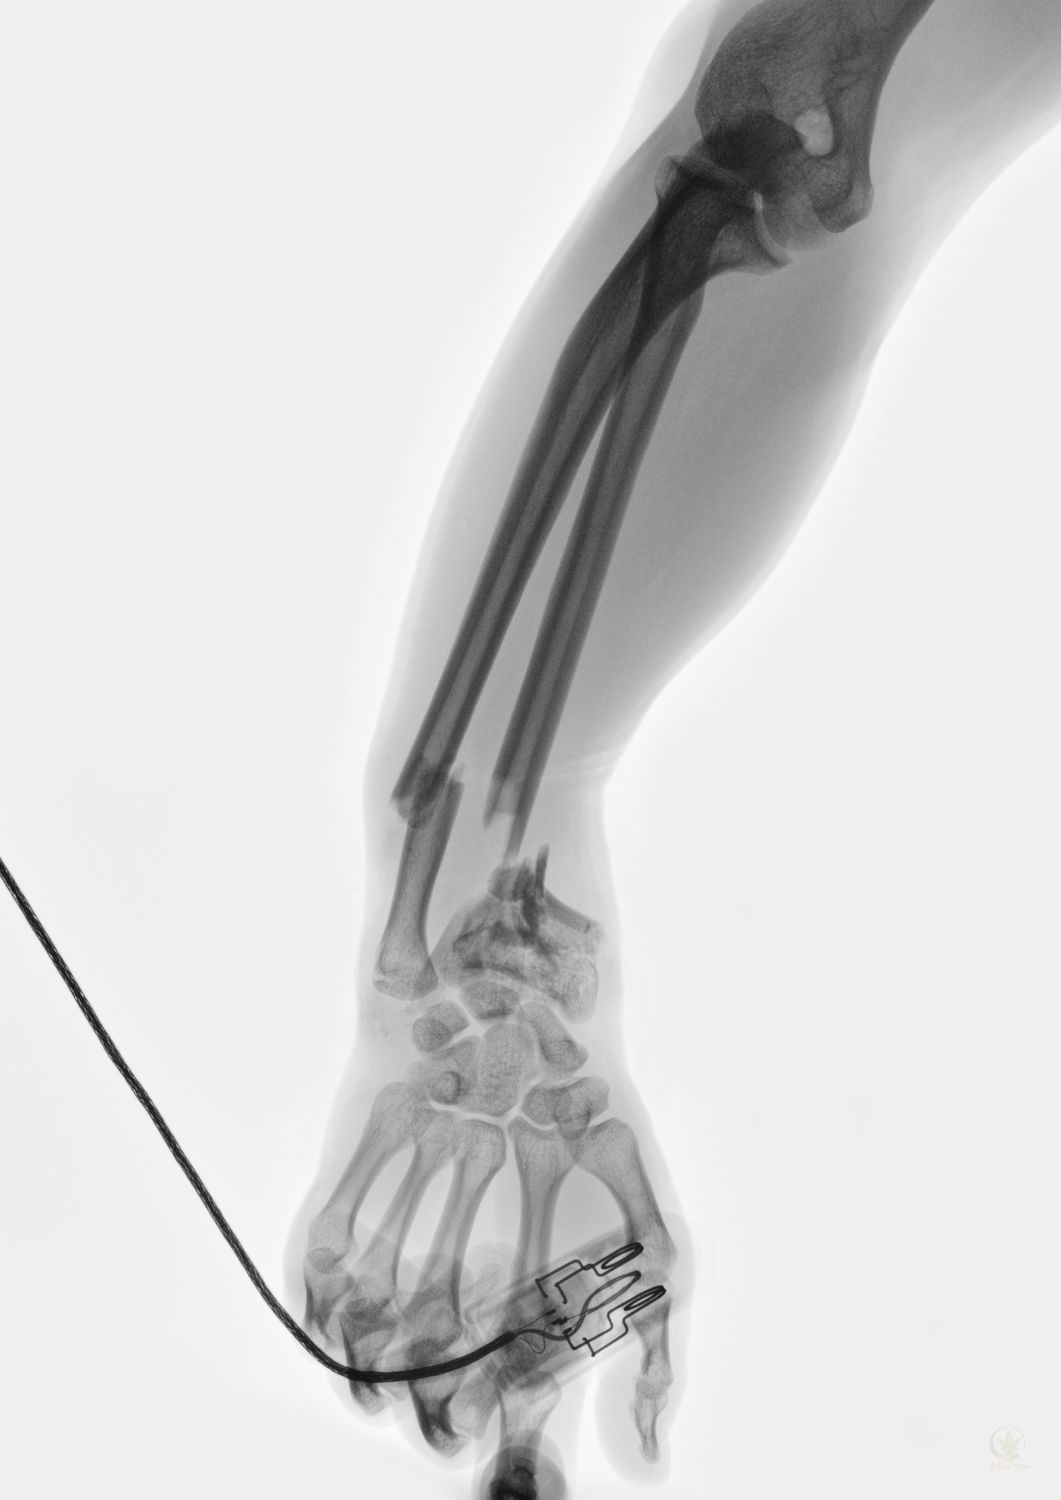

Las fracturas óseas son un problema de salud pública que afecta a millones de personas en todo el mundo. El dolor y la larga recuperación son solo algunos de los desafíos que enfrentan los pacientes. Sin embargo, un nuevo estudio de la Facultad de Medicina de Penn State ofrece una esperanza renovadora.

Los investigadores de Penn State han descubierto que los cannabinoides, como el cannabidiol (CBD) y el cannabigerol (CBG), podrían ser una alternativa eficaz para el tratamiento de fracturas óseas. En un estudio publicado en el Journal of Bone and Mineral Research, se observó que el CBD y el CBG no solo alivian el dolor de manera comparable a los medicamentos antiinflamatorios no esteroides (AINE), sino que también aceleran la curación de las fracturas.

Este hallazgo es particularmente importante porque los AINE, si bien son efectivos para el dolor, pueden interferir con el proceso de curación. El CBD, por otro lado, no solo reduce el dolor sin afectar la curación, sino que también promueve la regeneración ósea.

Los investigadores utilizaron técnicas avanzadas como la microscopía de inmunofluorescencia, la tomografía por microcomputadora y las pruebas biomecánicas para estudiar los efectos del CBD y el CBG en la curación de fracturas. Observaron que los cannabinoides:

- Aumentan la cantidad de progenitores óseos periósticos, que son células que se convierten en células óseas especializadas y ayudan a la formación del tejido óseo.

- Aceleran el proceso de absorción de minerales por parte del cuerpo, lo que fortalece el hueso recién formado.

- Resultan en una mayor cantidad de volumen óseo y densidad mineral, lo que lleva a la formación de un hueso funcional y saludable.